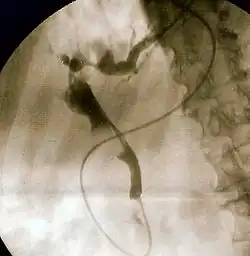

| Duodenoscopy image of pus extruding from Ampulla of Vater, indicative of cholangitis | |

The gold standard test for biliary obstruction is still endoscopic retrograde cholangiopancreatography (ERCP). This involves the use of endoscopy (passing a tube through the mouth into the esophagus, stomach and thence to the duodenum) to pass a small cannula into the bile duct. At that point, radiocontrast is injected to opacify the duct, and X-rays are taken to get a visual impression of the biliary system. On the endoscopic image of the ampulla, one can sometimes see a protuberant ampulla from an impacted gallstone in the common bile duct or the frank extrusion of pus from the common bile duct orifice. On the X-ray images (known as cholangiograms), gallstones are visible as non-opacified areas in the contour of the duct. For diagnostic purposes, ERCP has now generally been replaced by MRCP. ERCP is only used first-line in critically ill patients in whom delay for diagnostic tests is not acceptable; however, if the index of suspicion for cholangitis is high, an ERCP is typically done to achieve drainage of the obstructed common bile duct.[7]